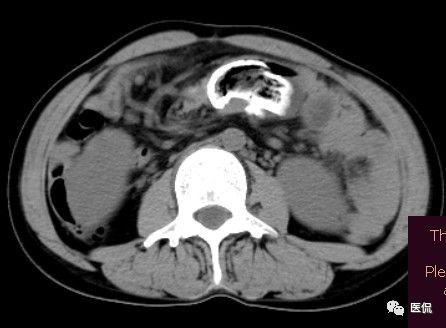

女 40岁 ,10年前做个剖腹产术。之后到现在一直感觉肚子疼,去很多医院做检查 诊断肠结核,经过反复抗结核治疗。病人10年瘦了几十斤。

腹腔内残留的纱布在人体内引起渗出或液化坏死并纤维包裹形成异物性脓肿(纱布瘤)。纱布瘤的影像特点:圆形或卵圆形肿块,较大,有完整包膜,薄壁,较少的情况下为厚壁,边界较完整,增强后薄膜可以持续强化。不同时期的纱布瘤可以有不同表现:早期(10个月或半年内)多表现为蜂窝状;2~5年内一般表现为囊性飘带状;10~20年之后则为实性软组织密度,包膜钙化呈钙化网状结构。手术过程中残留在人体内的医用纱布所形成的肿瘤样病变。